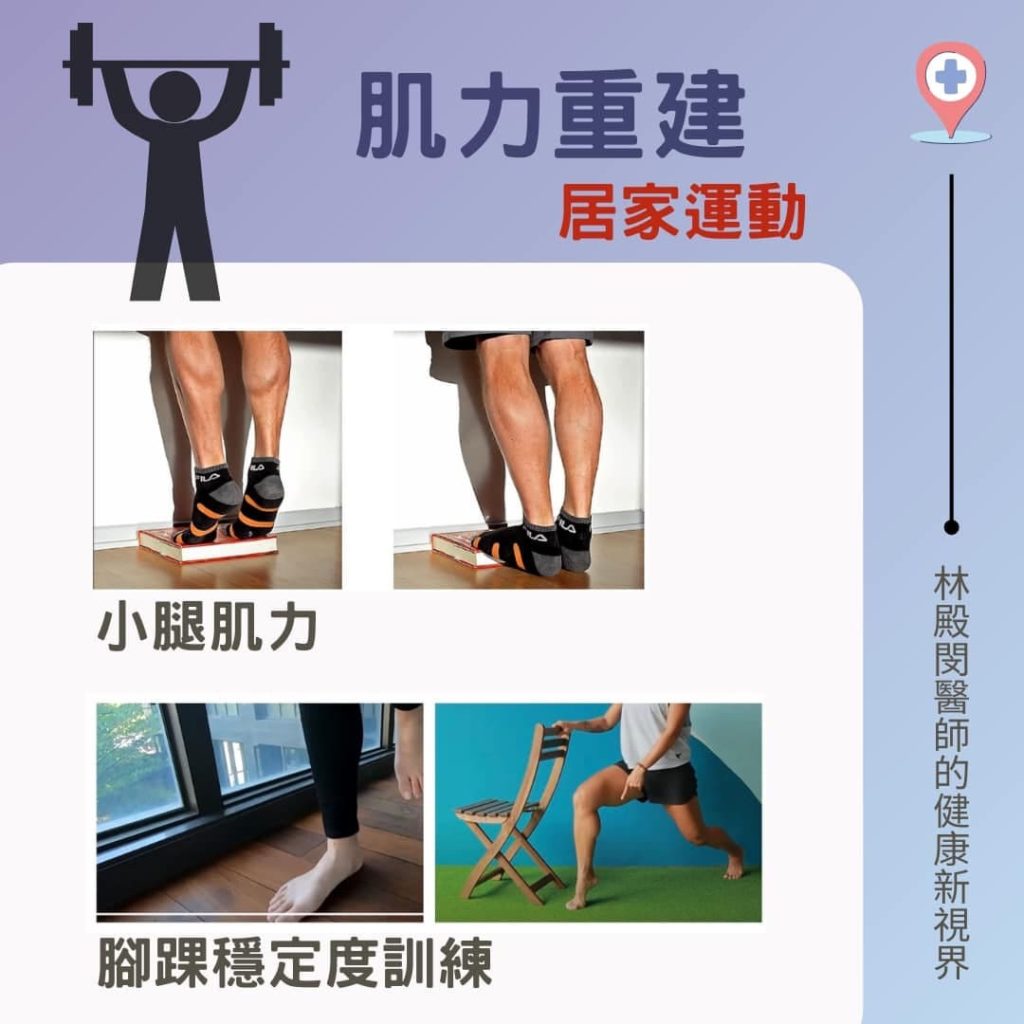

因此林醫師建議蘇小姐使用護踝或支撐帶,以減少關節活動並提供穩定度。 待扭傷的腳踝消腫之後,即可開始進行運動治療以增強足踝周圍肌力、關節活動度以及靈活度訓練。若像蘇小姐一樣有運動需求的人,還需要在治療師的指導下,進行平衡和協調等功能性訓練,以減少再次受傷的風險。

爾後回診,蘇小姐腳踝疼痛漸漸改善,在症狀改善後,她也開始逐步恢復運動,在運動中也使用護踝避免再度受傷。

反覆性腳踝扭傷是一種很常見的運動傷害, 但需要經過適當的診斷、完整的治療計畫以及預防策略,才能有效根治並減少後續再次受傷的風險